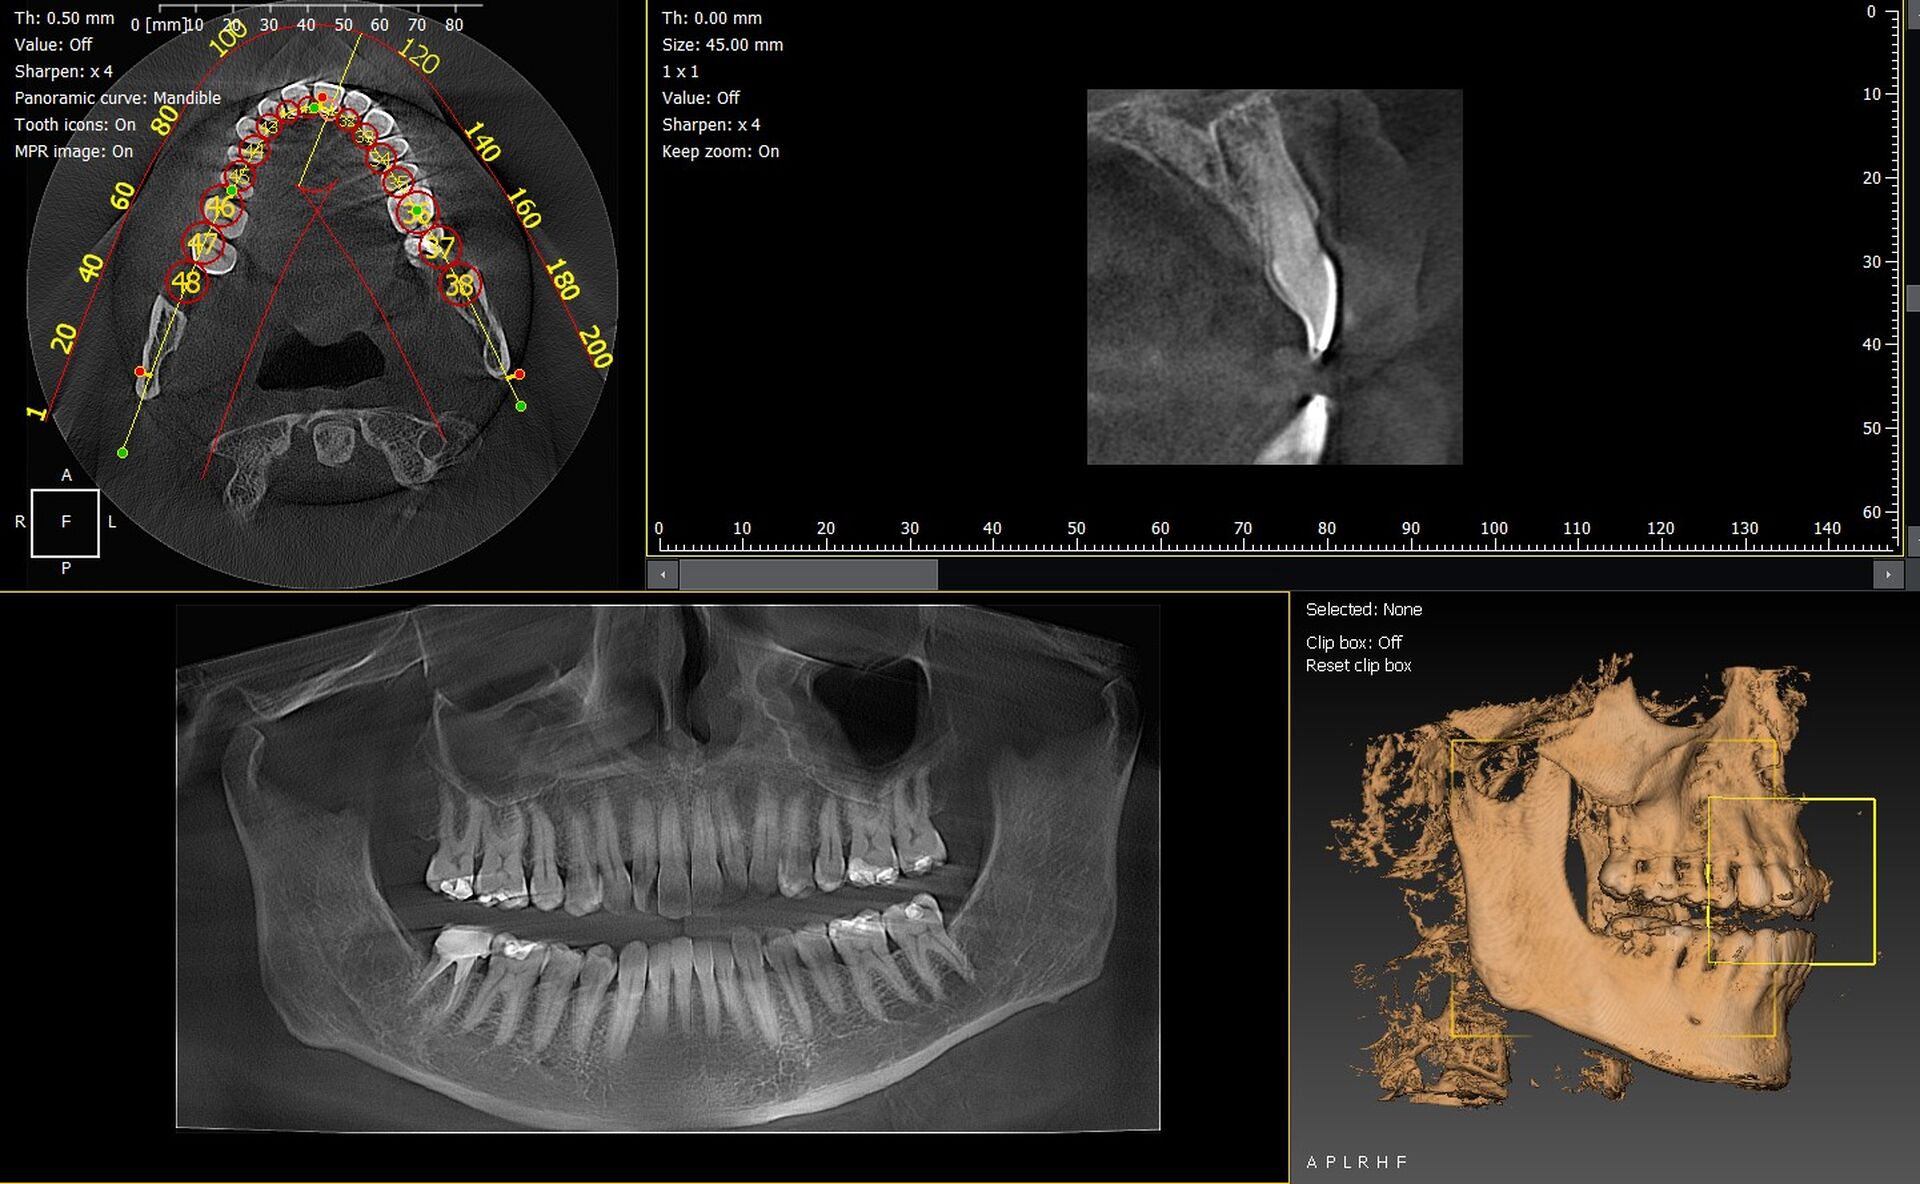

Les cabinets dentaires d’Orange, au cœur du Vaucluse (84), modernisent leur matériel d’imagerie pour améliorer la précision diagnostique et optimiser leurs flux de travail. Parmi les équipements les plus performants, les panoramiques CBCT 3D VistaVox de Dürr Dental et l’Owandy I-Max 3D offrent une qualité d’image exceptionnelle et une grande facilité d’utilisation.

VistaVox 3D : précision et champ focal optimisé

Le VistaVox se distingue par :

• un volume d’imagerie adapté à l’arcade dentaire,

• une grande précision pour l’implantologie, l’endodontie et la chirurgie,

• une réduction de dose maîtrisée,

• un positionnement rapide du patient.

Owandy I-Max : compact, moderne et polyvalent

L’Owandy I-Max 3D est particulièrement apprécié pour :

• son format mural compact, idéal dans les cabinets urbains du 84,

• son excellente qualité d’image en 2D et 3D,

• son interface simple et rapide à apprendre,

• une installation rapide et peu contraignante.